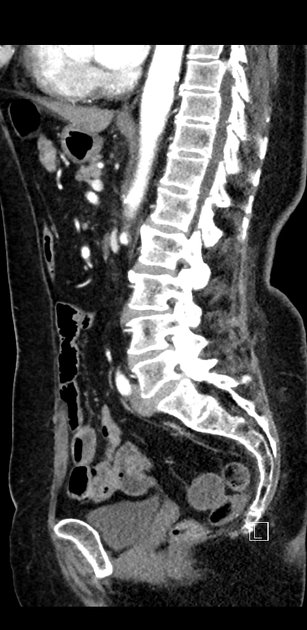

Sagittal C+ delayed

Sagittal C+ arterial phase